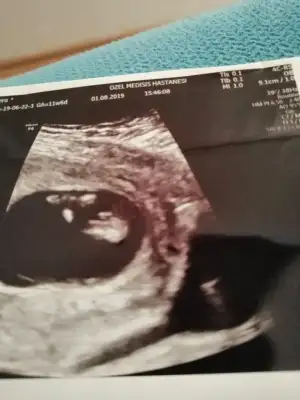

Senin usg de bebeğin duruş pozisyonundan dolayı emin olamadım canım.kesin demiyim ama son kararım kızBen hiç anlamıyorum ama yrn kontrolüm var eğer usg bakarsa daha net görünür sanırım yine resim koyarım![]()

Kız benceBana da yorum yaparmisnz

Insallah canm ya iki dktrda erkege benzetti ama kesin deil dedi alisveris yapma dedilerKız bence

Valla kesin konuşmayayım tabi.iyice emin olduklarıma kesin diyorum ama bu usg ye kesin diyemiyorum.ben bu usg de kıza benzettim.ama erkek te olabilir.nubu kıza,kafa yapısı erkeğe benziyor.hayırlısını versin rabbimInsallah canm ya iki dktrda erkege benzetti ama kesin deil dedi alisveris yapma dediler